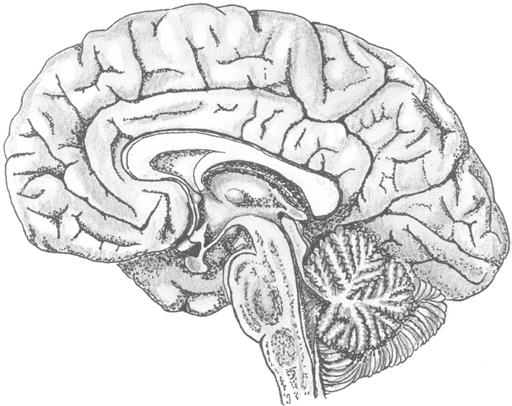

Podívejme se nyní na jednotlivé části našeho mozku a připomeňme si je ve stručném orientačním přehledu. Jedná se o mozkový kmen, mozeček, mezimozek a koncový mozek.

MOZKOVÝ KMEN (truncus cerebri) je bazální částí mozku, která navazuje přímo na páteřní míchu a sestává ze tří částí. Od úrovně velkého týlního otvoru (která je hranicí mezi mozkem a páteřní míchou) směrem vzhůru jsou to: prodloužená mícha (medulla oblongata), Varolův most (pons Varoli) a střední mozek (mesencephalon).

Na úrovni mozkového kmene najdeme jádra většiny hlavových nervů. Mozkový kmen je místem řízení a regulace základních životních funkcí (jako je srdeční činnost a dýchání), vitálních reflexů (polykání, zvracení, kýchání apod.) i geneze bdělosti. Prochází tudy velké množství vzestupných a sestupných nervových vláken (nervových drah) propojujících řadu oblastí mozku a páteřní míchy.

Mozkovým kmenem prochází 3D síť propojených neuronů, která se označuje jako retikulární formace (formatio reticularis). Ascendentní (vzestupný) aktivační systém retikulární formace vysílá vlákna do vyšších etáží mozku a mimo jiné hraje významnou roli v genezi bdělosti.

MOZEČEK (cerebellum) naléhá na zadní stranu mozkového kmene. Je tvořen dvěma mozečkovými polokoulemi (hemispheria cerebelli) a nepárovou středovou částí, které říkáme mozečkový červ (vermis cerebelli).

Na jejich povrchu najdeme mozečkovou kůru tvořenou třemi vrstvami složitě propojených nervových buněk. V hloubce leží bílá hmota mozečková (tvořená nervovými vlákny) a rovněž mozečková jádra (tvořená shluky těl nervových buněk).

Spojení mozečku s ostatními částmi mozku zajišťují tři mohutné svazky nervových vláken – horní, střední a dolní mozečkové stonky (pedunculi cerebelli craniales, mediales et caudales).

Mozeček obrazně označujeme jako „šedou eminenci mozku“, neboť dostává informace z řady oblastí mozku i těla a sám vstupuje do mnoha funkcí. Známý je podíl mozečku na řízení hybnosti, uplatňuje se ale i v procesech učení, paměti, regulace chování, prožívání apod.

V mozečku najdeme různé typy nervových buněk. Jedním z nich jsou i Purkyňovy buňky – velké neurony s typickým bohatým větvením svých výběžků.

levá mozečková polokoule

mozečkový červ (vermis cerebelli)

pravá mozečková polokoule

Obr. 2.11 Mozeček

paravermální oblasti

MEZIMOZEK (diencephalon) je uložen zhruba ve středu mozku mezi mozkovými polokoulemi. Skládá se ze dvou částí – párového talamu a nepárového hypotalamu.

• Talamus (thalamus) je tvořen dvěma tělesy vejčitého tvaru, která mezi sebou uzavírají III. komoru mozkovou. Talamus hraje roli „ústřední přepojovací stanice“, v každém okamžiku sem přichází obrovské množství informací senzitivních, motorických a autonomních. Právě tady dochází k jejich třídění a přepojování do dalších oblastí mozku.

• Hypotalamus (hypothalamus) je struktura uložená vepředu ve středu pod oběma talamy (tvoří dno zmíněné III. komory mozkové). Plní dvojitou funkci – jednak je významným nervovým ústředím, které dominantně řídí vnitřní orgány a tělesné pochody (tedy autonomní funkce), jednak je zapojen do hypotalamo-hypofyzárního systému, v rámci kterého funguje jako důležitý hormonální producent. Právě hypotalamus rozhodujícím způsobem reguluje stálost vnitřního prostředí (homeostázu), ovládá projevy emocí na úrovni těla, podílí se na řízení biorytmů (např. střídání bdění a spánku) atd.

Nepřekvapí nás, že vnitřní struktura obou částí mezimozku je dále členěna na dílčí specifické podoblasti. Např. v talamu popisujeme několik skupin specifických jader – uskupení těl neuronů s určitou funkcí.

KONCOVÝ MOZEK (telencephalon) představuje nejobjemnější část lidského mozku. Je tvořen dvěma mozkovými polokoulemi (hemisperia cerebralia), které spolu velmi úzce spolupracují.

• Pravá mozková polokoule (hemisphera cerebri dextra) zpracovává především podněty s emočním doprovodem (včetně umění), chápe prostorové vazby, vládne představivostí.

• Levá mozková polokoule (hemisphera cerebri sinistra) reprezentuje zejména logické, matematické, analytické a technické myšlení a vládne také řečí.

Propojení obou polokoulí obstarávají mohutné svazky nervových vláken – mozkové komisury (commissurae cerebri). Největší komisurou je vazník neboli kalózní či bílé těleso (corpus callosum).

Vlastní hmota koncového mozku je členěna na šedou a bílou:

• Šedá hmota koncového mozku tvoří mozkovou kůru (cortex cerebri) na povrchu a podkorové struktury uvnitř hemisfér (sem patří např. bazální jádra a podkorové části limbického systému – jmenovitě amygdala a hipokampus).

• Bílá hmota koncového mozku leží v hloubce. Je tvořena gigantickým množstvím nervových vláken.

Povrch mozkových polokoulí je členěn řadou rýh a brázd do jednotlivých mozkových závitů – gyrů (gyri cerebri, jednotné číslo gyrus cerebralis). Popisujeme celkem pět mozkových laloků (lobi cerebri, jednotné číslo lobus cerebralis). Mozková kůra jednotlivých laloků obsahuje specifické korové oblasti (s jasně vymezenou funkcí) a dále asociační korové oblasti (které hrají roli propojovací, integrující a koordinující).

Obr. 2.15 Pohled na vnitřní (mediální) stranu mozku